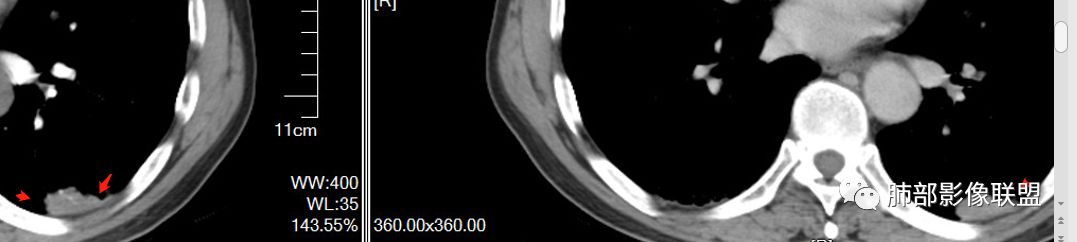

南边老师论述:    分叶凹陷的地方有血管,支气管进去,这个价值很大,后来引申到血管、支气管从凹陷的地方进去就叫脐凹征,就像番茄柄🍅,辣椒柄、苹果柄🍎一样的。后来就把这个做为脐凹征,95%以上的特异性。如下例:

后来发现胸膜牵拉,由远端凹陷的地方进去,他的价值也很大,诊断腺癌,几乎很少失误,后来把这个也纳入到脐凹征里。由凹陷处进入的胸膜牵拉征,由凹陷处进去的血管,都属于脐凹征。原理是由凹陷处进去的血管,因为肿瘤膨胀生长,生长过程中遇到血管,支气管区域受阻,边缘代偿性生长,膨胀的更厉害了,所以局部凹陷,前提是血管、支气管肯定在肺门侧,不会在远端有一条血管阻碍他的,可能性太小了。

脐凹征,支气管、血管引起的在肺门侧,因肿瘤生长在近端膨胀受阻的,病灶本身围绕支气管、血管周围包绕的不算,只有进去其中受阻的才算。